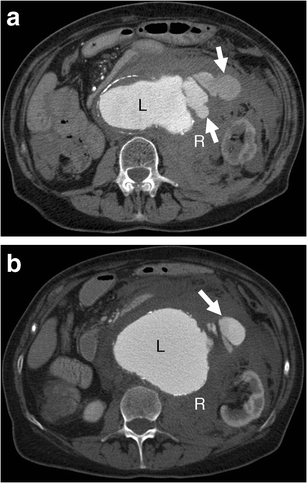

Contrast extravasation. a-b Axial enhanced CT of a 75-year-old woman demonstrates active contrast extravasation (white arrows) from the aneurysm lumen (L) into the retroperitoneal space with massive retroperitoneal haematoma (R)